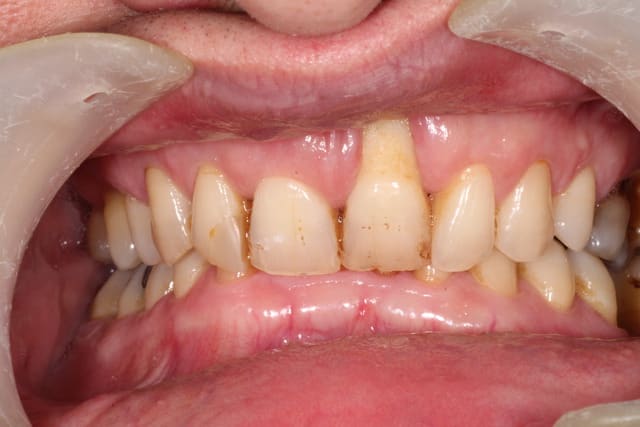

Patient adressé par une consœur pour sa 21. Fume un paquet.

Pas vraiment de pb paro, à part un bourrage entre 26 et 27 ayant entrainé une perte osseuse conséquente.

Grosse supra.

Pour moi la bouche est dysfonctionnelle. Évidente supraclusion mais pas seulement.

La déviation de la mandibule à gauche signe une mastication unilatérale à gauche. Si tu as une pano on verra le condyle gauche plus volumineux. Ce qui explique pourquoi 21 et pas 11.

quelques nouvelles photos :